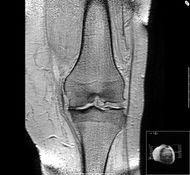

لقد تغيرت نظرتنا في العقد الماضي لتركيب ووظيفة الغضروف تغيرا مهما فأصبحنا نعتبر عملية المرض في الفصال العظمي على أنها طريقة بناء أكثر منها طريقة تنكس (Degeneration) فمن المعروف الآن أن الغضروف عبارة عن نسيج حيوي مصنوع من النوع الثاني من ألياف الكولاجين والبروتيوجليكان وخلايا غضروفية وماء وفي الحقيقة يمثل الماء نسبة تصل من 80 إلى 90 من الغضروف ومن هذا فإن عبارة إننا نمشي على الماء صحيحة لحد ما إن جزيئات البروتيوجليكان التي تميل إلى اجتذاب الماء هي في الواقع الجزيئات الكبيرة التي تملأ فراغ المطرق (Matrix) ولذلك تسمح لغضروف المفصل بتغيير شكله بطريقة انعكاسية مرتجعة (Reversible deformation) ويظهر شكلا 2 و3 غضروفا متأثرا بالفصال العظمي وغضروفا سليما .

ومن المفاصل الرئيسية الأخرى التي تتأثر بالفصال العظمي هي المفصل الأول بين سلاميات القدم ومفصل الفخذ والركبة. وهو ينتشر بدرجة خاصة في هذه المفاصل في كبار السن ولكن التنبؤ به مختلف ويعتمد على الجزء المصاب من المفصل وقد تكون الإصابة من ناحية واحدة أو ناحيتين. ويمكن تقسيم الفصال العظمي لمفصل الفخذ إلى مجموعات ثانوية (Subsets) هي علوي جانبي وإنسي وحلقي وكذلك يمكن تقسيم الفصال العظمي لمفصل الركبة إلى مرض القسم الإنسي الجانبي ومرض المفصل الظنبوبي الفخذي أو مرض المفصل الفخذي الرضفي وكل من هذه الحالات قد تتصرف بطريقة مختلفة من ناحية بداية المرض وتقدمه على الرغم من أن العملية المرضية هي نفسها. وقد تكون هناك إصابة سابقة لأعوام كثيرة مضت في حالة الفصال العظمي للركبة وقد تصاب بعض المفاصل الأخرى الكبيرة بالفصال العظمي بما فيها مفصل الكتف والكاحل ولكن لابد أن توضع بعض الأسباب الأخرى في الاعتبار إذا كانت هذه المفاصل هي البذرة الأساسية للمرض.

إن الفصال العظمي يتم تشخيصه إكلينيكيا ومن الممكن أن يتم إثباته عن طريق التصوير بالأشعة السينية ومن المهم أن نتذكر أن هناك علاقة ضعيفة بين الملامح الإكلينيكية والملامح الشعاعية ومن المنظور البحثي تتم الآن دراسة عدد كبير من الواسمات الكيميائية الحيوية وتقنيات التصوير الشعاعي لكي يتم تقييم الفصال العظمي بدقة وقد تم استخدام تقنيات التصوير مثل فائق الصوت والأشعة السينية المكبرة والتصوير بالأشعة الومضانية (Scintigraphy) لكي تعطى صورة أفضل للغضروف وما تحته من عظام ويعطينا منظار المفصل المصغ ر وباستخدام منظار المفصل الرفيع الجديد للرؤية المباشرة لسطح الغضروف ومن الممكن في المستقبل أن يعطينا وسيلة لتقييم تقدم المرض ولكن لا توجد دواع في الوقت الراهن لاستخدام تقنيات التصوير هذه في التشخيص السريري.